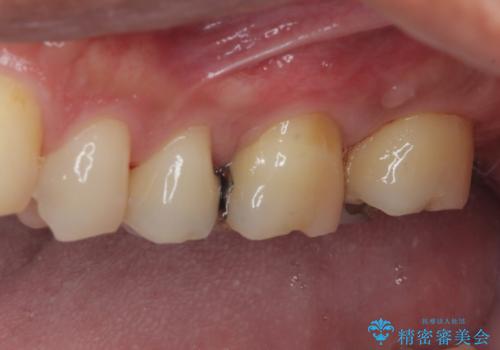

放置した欠損部 奥歯の即時荷重インプラント治療

- 左下欠損部のインプラント治療を希望して来院された患者様です。

左下の欠損部を長期間欠損を放置していたことで、咬み合う上の奥歯が動いてしまっている状態でした。

インプラント部は埋入とともに仮歯を装着し、同時に上顎奥歯の部分矯正を開始することとしました。

理想的な咬み合わせに改善した上で、インプラント補綴治療を行うこととしました。